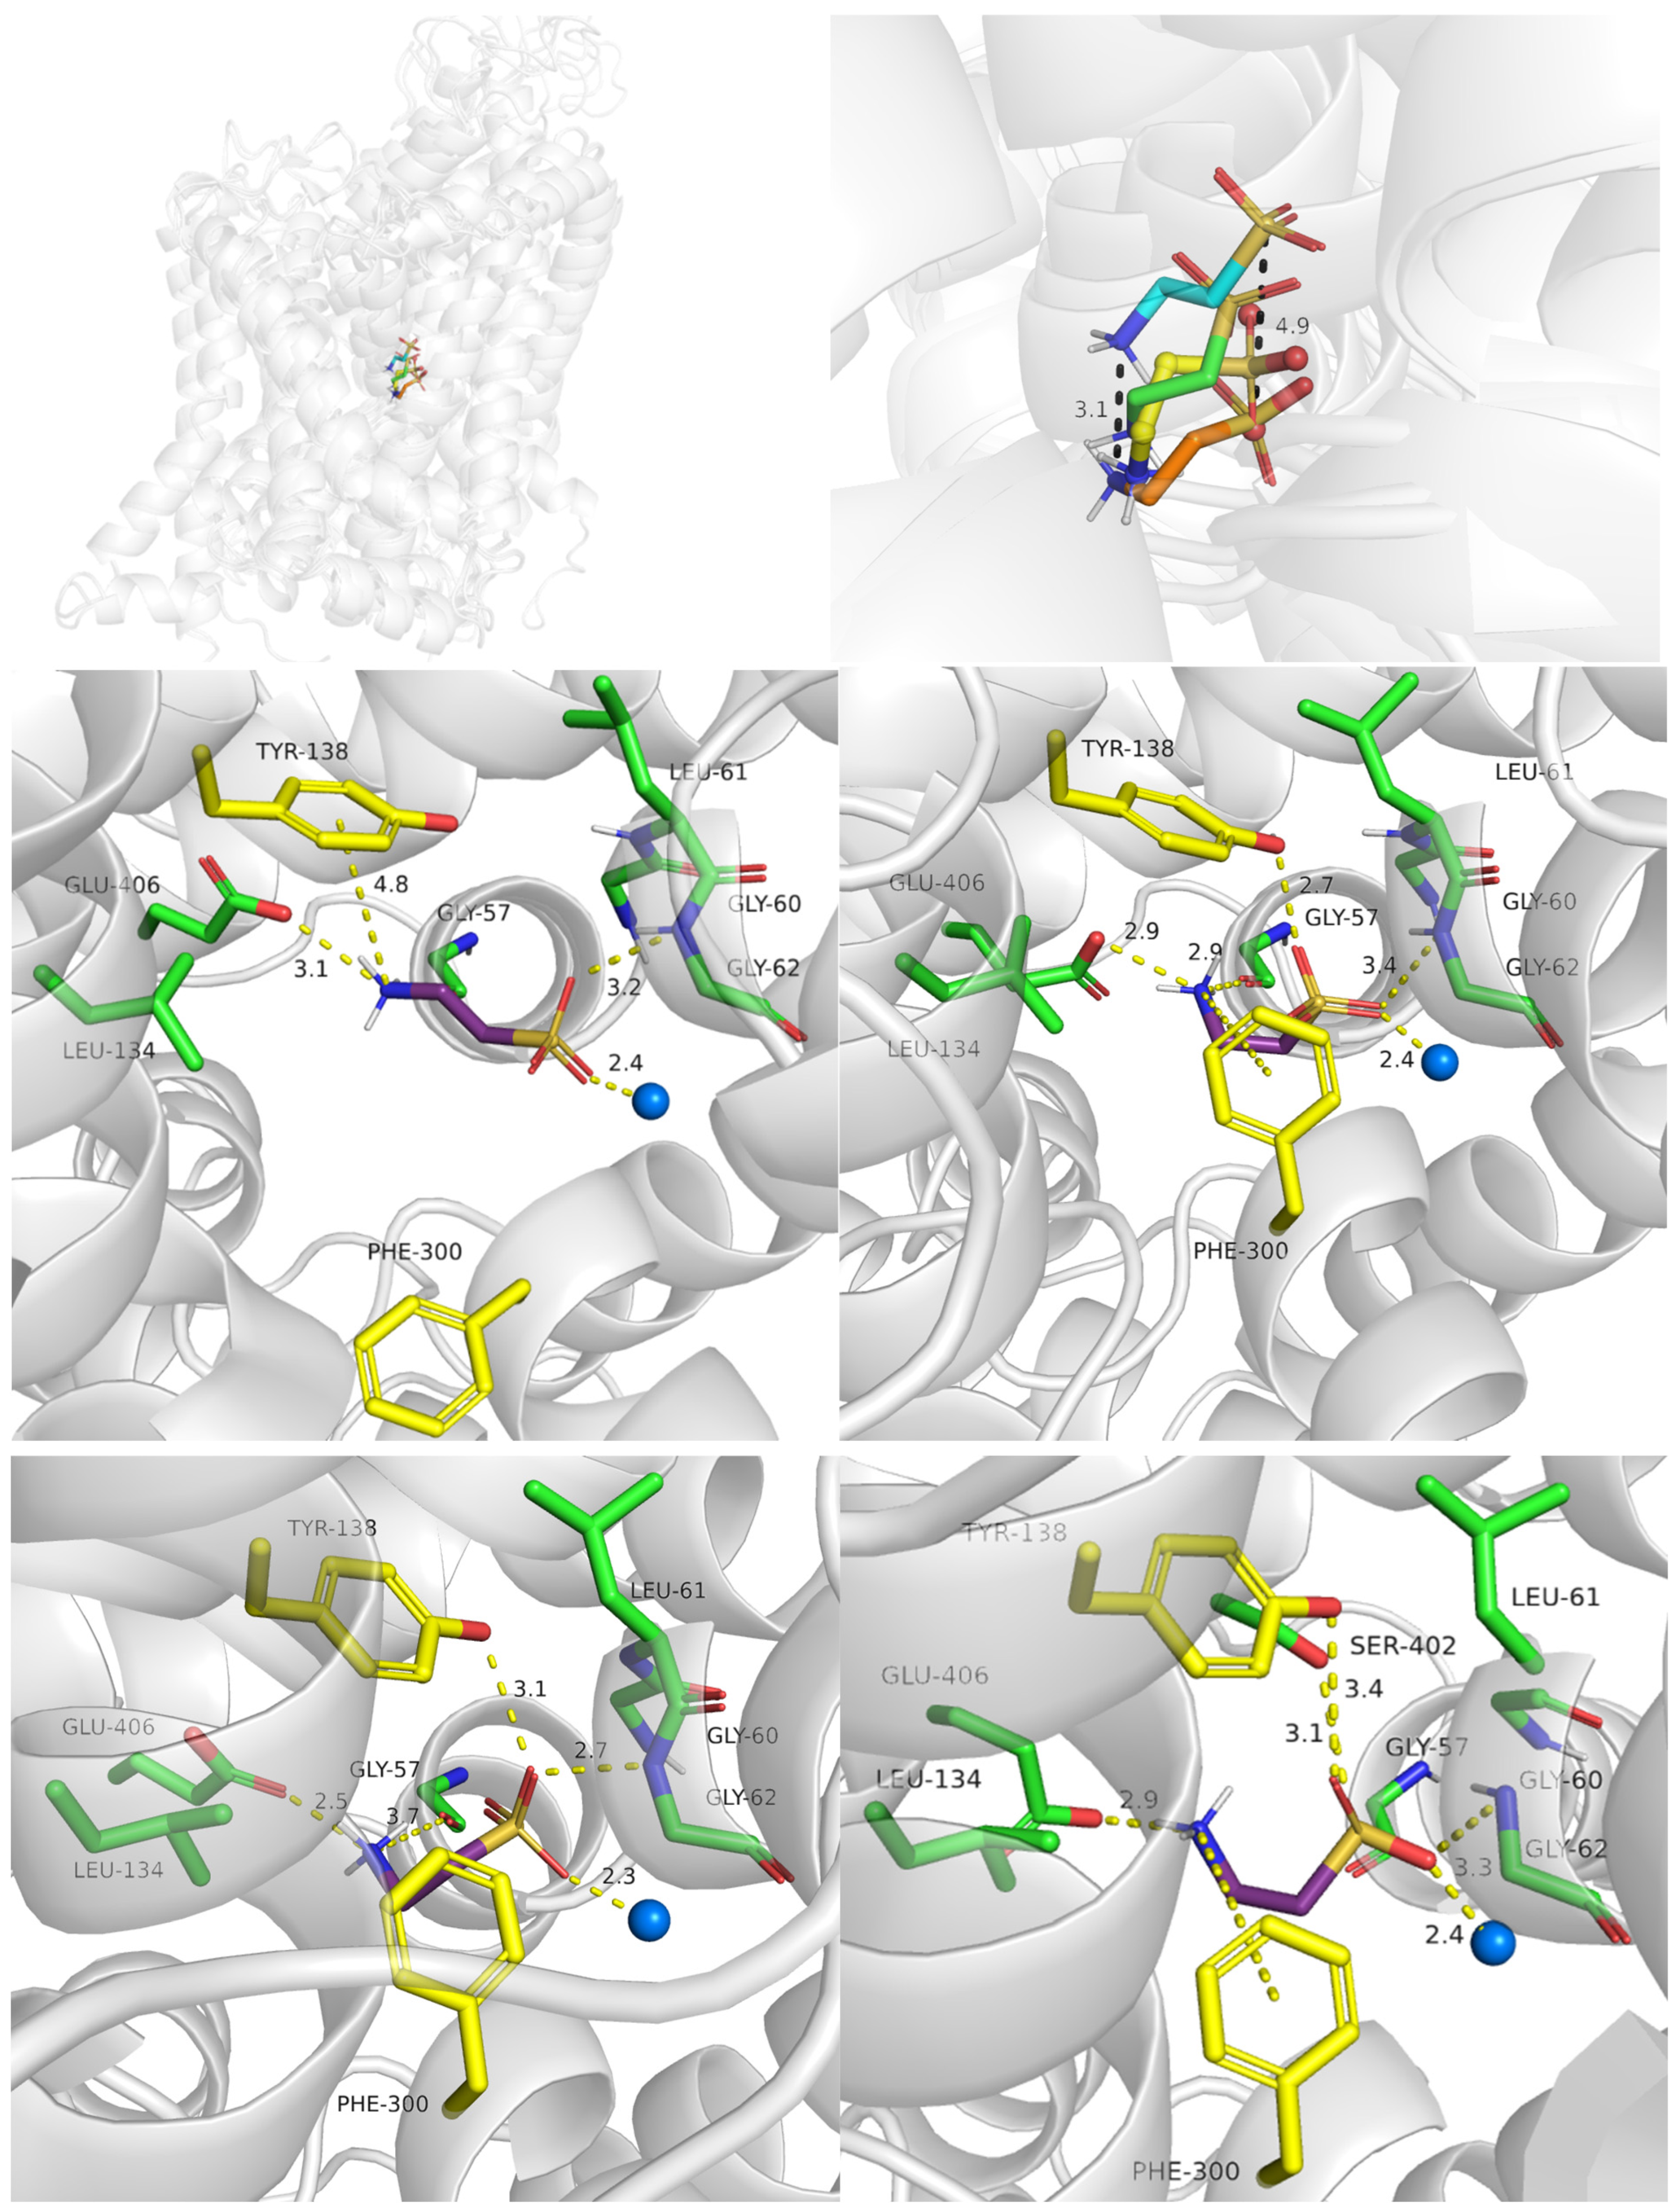

2.3. TauT Docking Studies

2.3.1. TauT Ligands Binding Mode

2.3.2. Binding of Taurine Transporter Inhibitors

2.4. Role of Mutations in Taurine Transporter

2.4.1. Glu406 Is Crucial for SLC6A6 Transporter Activity

2.4.2. Importance of Gly57 and Leu306 for SLC6A6 Activity